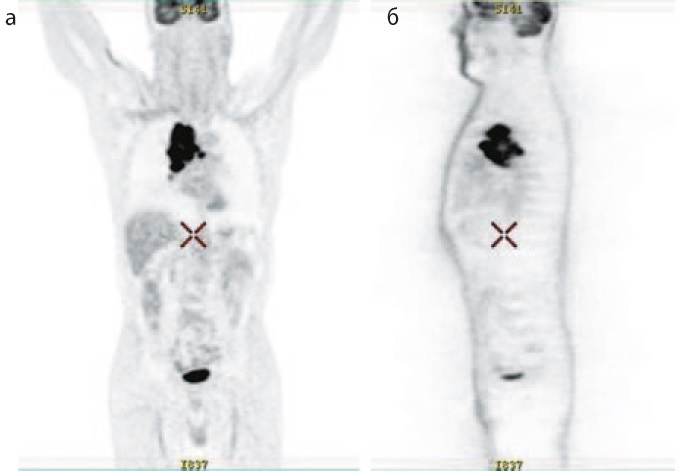

На контрольном ПЭТ/КТ после 4 курсов терапии зарегистрирован частичный ответ (рис. 5). Ранее описываемый конгломерат в средостении не определяется. Отмечено наличие множественных паратрахеальных паравазальных, бифуркационных бронхопульмональных лимфоузлов до 19×23 мм с метаболической активностью SUVmax 5,3.

Рис. 5. ПЭТ/КТ после 4 курсов терапии (15.02.2020). Частичный ответ.

Fig. 5. PET/CT after 4 courses of therapy (15.02.2020). Partial answer.

С марта 2020 г. и по настоящее время проводится терапия атезолизумабом в монорежиме в дозе 1200 мг с интервалом в 21 день. НЯ, связанные с ХТ, разрешились. Иммуноопосредованных реакций не отмечается. Переносимость удовлетворительная. По данным контрольных обследований ПЭТ/КТ сохраняется частичный ответ. Динамика изменения таргетных очагов представлена в табл. 2.